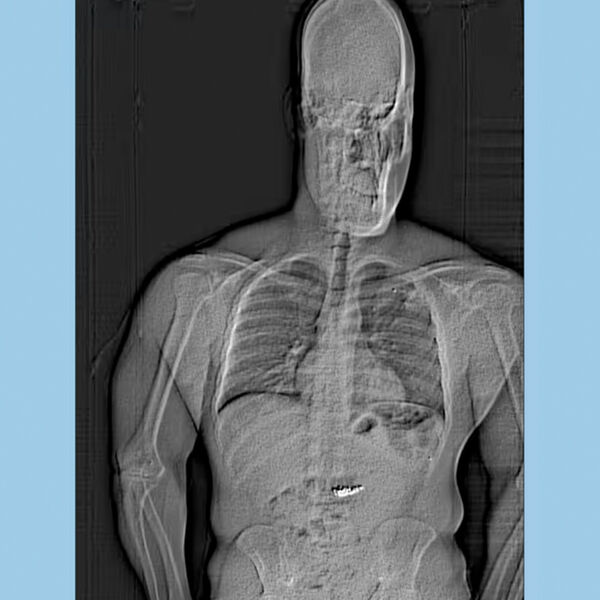

Подозреваемого удалось вскоре задержать. На сканировании, куда отправили Джейтана Гилдера, выяснилось, что в его желудке есть инородные предметы.

«Позже, после того как бриллианты были удалены из его организма, мы смогли отвезти их в Tiffany & Co., где их очистили, и главный ювелир подтвердил, что надпись и серийные номера соответствуют украденным изделиям», — отметили в полиции.